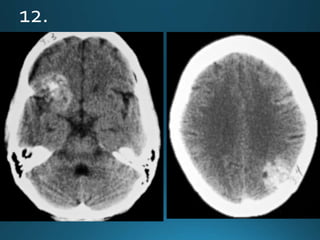

Sturge-Weber syndrome (SWS), or encephalotrigeminal angiomatosis, is a phakomatosis

characterised by facial port wine stains and pial angiomas

CT

detects subcortical calcification at an earlier age than plain film and can also demonstrate

associated parenchymal volume loss

'tram-track' subcortical calcification

MRI

T1: signal of affected region largely normal, with anatomic volume loss evident at older age

T1 C+ (Gd)

prominent leptomeningeal enhancement in affected area

T2

low signal in white matter subjacent to angioma representing

calcification later in life

abnormal deep venous drainage seen as flow voids

GE/SWI/EPI: sensitive to calcification, seen as regions of signal drop out